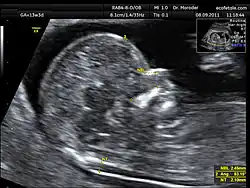

Clarté nucale

La clarté nucale, petite zone anéchogène (ne renvoyant pas d'écho en échographie) située sur le crâne d'un fœtus humain pendant le premier trimestre de grossesse, permet de dépister certaines anomalies congénitales, en particulier la trisomie 21.

La clarté nucale, comme son nom l’indique, se situe au niveau de la nuque du fœtus. Elle est due à un petit décollement entre la peau et le rachis et correspond à une zone dite anéchogène (c’est-à-dire qui ne renvoie pas d’écho lors de l’examen). Tous les fœtus présentent une clarté nucale au cours du premier trimestre, mais cette clarté disparaît ensuite.

La mesure de la clarté nucale[6] doit avoir lieu au cours de la première échographie de la grossesse, c’est-à-dire entre la 11e semaine et 13 semaine + 6 jours d’aménorrhée. Il est impératif que l’examen soit fait à cette période, car passé trois mois, la clarté nucale disparaît.